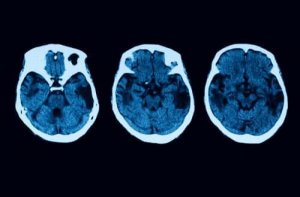

Diagnostische tests houden hier echter niet op. Om twijfel weg te nemen, zullen er andere neurologische tests zijn, zoals MRI’s en tomografieën. Als alles erop wijst dat je mogelijk posterieure corticale atrofie hebt, dan zijn er verschillende behandelingen waar je uit kunt kiezen.